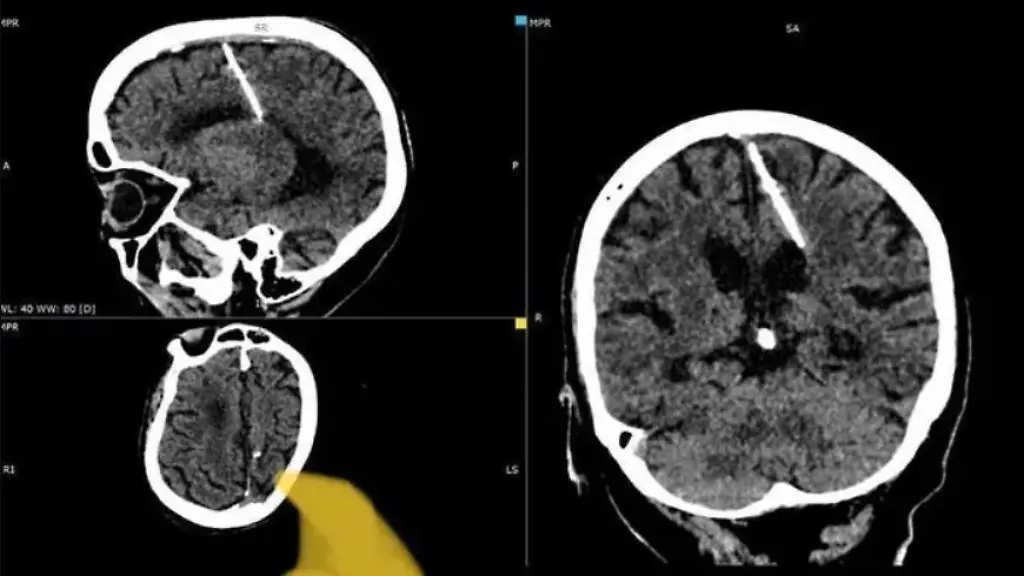

Bei einer ärztlichen Untersuchung sind Mediziner in Russland vermutlich einem Jahrzehnte zurückliegenden Mordversuch auf die Spur gekommen. Im Gehirn einer 80-jährigen Frau entdeckten die betreuenden Radiologen eine drei Zentimeter lange Nadel, teilten die örtlichen Gesundheitsbehörden mit.

Das Gesundheitsministerium der Region Sachalin schrieb in einem Telegram-Posting, dass es bei einer Computertomografie zu der Entdeckung gekommen war. Das Ministerium gab nicht genau an, wann die Ärzte den Fund gemacht haben, wies aber darauf hin, dass er im Jahr 2023 stattfand.

Die Nadel wurde demnach im linken Scheitellappen der ungenannten Frau gefunden, so das Ministerium. Die Ärzte glauben, dass die 80-jährige Frau das Opfer eines missglückten Kindermordes ihrer Eltern war.

"Die Nadel drang in ihren linken Scheitellappen ein, hatte aber nicht die beabsichtigte Wirkung - das Mädchen überlebte", so die örtliche Gesundheitsbehörde. Die Patientin habe nie über Kopfschmerzen aufgrund der Verletzung geklagt und sei auch jetzt nicht in Gefahr. Deshalb werde man auch nicht versuchen, die Nadel zu entfernen, da zu befürchten sei, dass sich ihr Zustand dann verschlimmern könnte. Weshalb die Frau untersucht wurde, wurde nicht mitgeteilt.